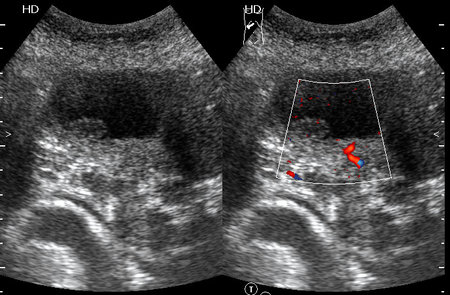

Женщина - пенсионерка. Жалобы скудные, дискомфорт в правом подреберье.